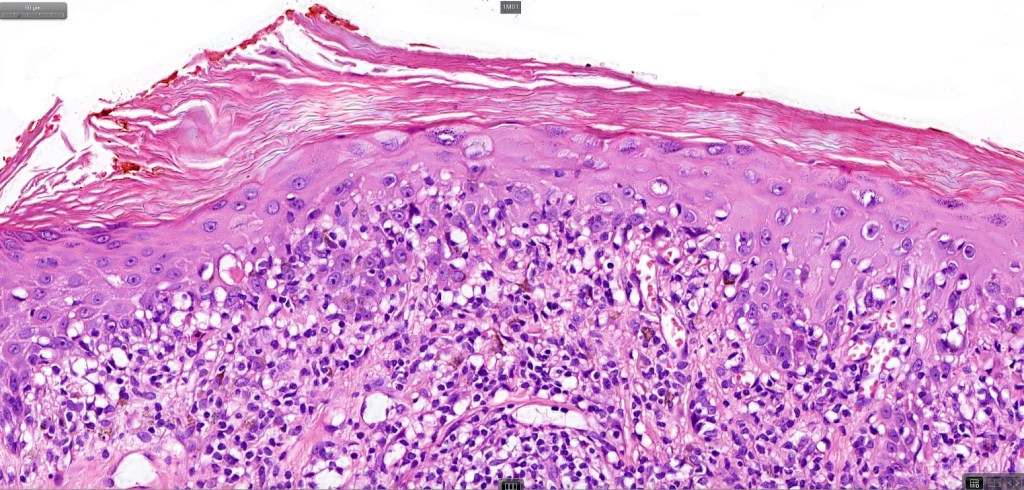

. Late lesions are charcterized by epidermal atrophy, papillary dermal fibrosis, pigment incontinence & a perivascular or interstitial lymphocytic infiltrate

•Hyperkeratosis +/- parakeratosis

•Interface change

•Pigment incontinence